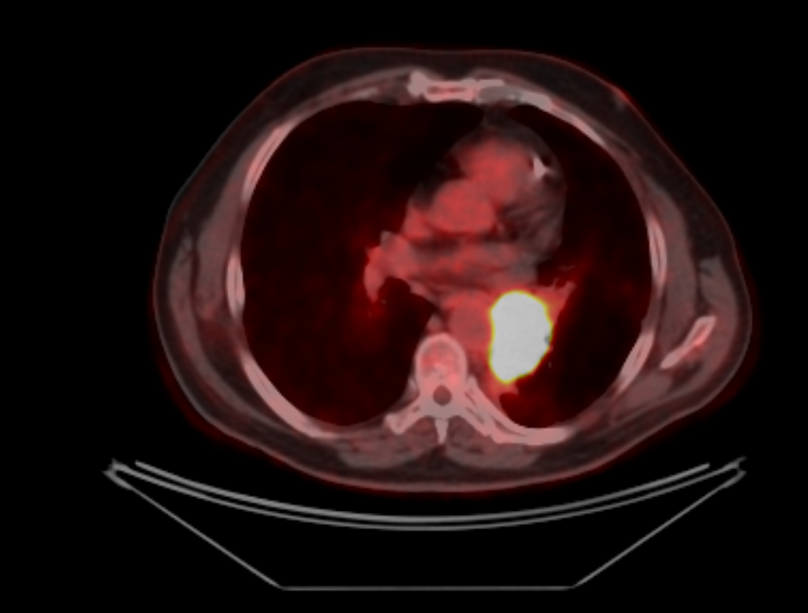

Заключение ПЭТ-КТ с ФДГ от 29.03.2022г:

- картина центральной опухоли левого легкого с признаками обструктивного пневмонита, мтс с поражением ипсилатеральных и подкаринальных лимфоузлов.

В воротах левого легкого определяется метаболически активный опухолевый узел с вовлечением главного, нижнедолевого, частично верхнедолевого бронхов, общими наибольшим размерами около 83 мм в аксиальной проекции и до 81 мм в краниокаудальной проекции, SUVmax=21.41. Опухоль располагается на расстоянии около 30 мм от киля трахеи с вовлечением левой легочной артерии (обхват около 50%) и тесным прилеганием к нисходящей аорте. Окружающая паренхима левого легкого с признаками воспаления. В правом легком очаговая и инфильтративная патология легких не определяется.Определяются метаболически активные медиастинальные лимфоузлы, наибольшими размерами/накоплением РФП: подкаринальной группы (7) до 10 мм, SUVmax=7.49; субаортальной группы (5) до 8 мм, SUVmax=4.70. Лимфоузлы ворот левого легкого четко не дифференцируются, вероятнее сливаются с основной опухолевой массой.

В воротах левого легкого определяется метаболически активный опухолевый узел с вовлечением главного, нижнедолевого, частично верхнедолевого бронхов, общими наибольшим размерами около 83 мм в аксиальной проекции и до 81 мм в краниокаудальной проекции, SUVmax=21.41. Опухоль располагается на расстоянии около 30 мм от киля трахеи с вовлечением левой легочной артерии (обхват около 50%) и тесным прилеганием к нисходящей аорте. Окружающая паренхима левого легкого с признаками воспаления. В правом легком очаговая и инфильтративная патология легких не определяется.Определяются метаболически активные медиастинальные лимфоузлы, наибольшими размерами/накоплением РФП: подкаринальной группы (7) до 10 мм, SUVmax=7.49; субаортальной группы (5) до 8 мм, SUVmax=4.70. Лимфоузлы ворот левого легкого четко не дифференцируются, вероятнее сливаются с основной опухолевой массой.

СД – сахарный диабет, ИБС – ишемическая болезнь сердца, фк - функциональный класс, ГБ – гипертоническая болезнь, ХСН – хроническая сердечная недостаточность, МРТ – магнитно-резонаснсная терапия, ПЭТ-КТ - позитронно-эмиссионная томография, ФДГ – фтордезоксиглюкоза, КУ – контрастное усиление, мтс – метастазы, SUV – стандартизированный уровень накопления.